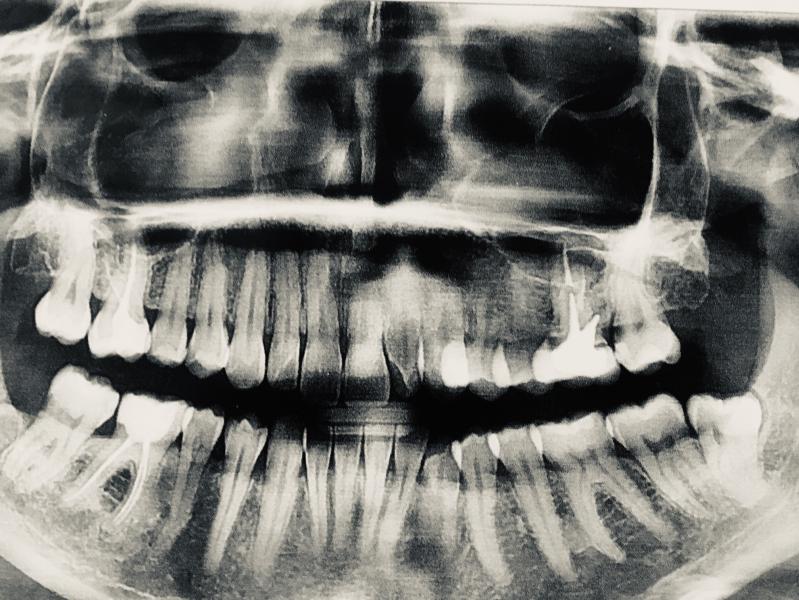

Несколько раз приходила, обсуждали удаление: неоднократно упоминала нюансы удаление предыдущего зуба, указывая, что зуб сложный. Мне сделали рентген. В первый визит удалять не стал по причине - стоматит на слизистой рта. Отправил на лечение.

В общем, неделю назад пришла на удаление. С третьим уколом обезболивающего почувствовала разливающееся тепло от зуба до рта, переходящее на шею: на сек 15-20 стало даже трудно дышать, но быстро прошло. Зуб распиливали на части и вытаскивались по кускам. Боли не было. Удаление длилось - 1ч. Сделали повторный рентген, чтобы убедится, что корни зуба удалены полностью.